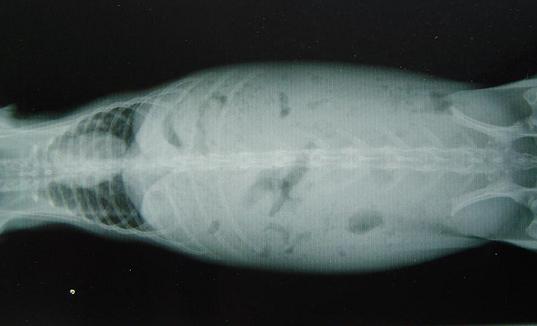

ついでのついでで…8月大不調に落ちた時に撮ったレントゲン画像。

胃腸の出口に問題あり…だったのですが、

何やよーわかりませんねぇ(;´Д`)

ちなみに、お腹辺りが真っ白なのは…シャギー脂肪が少ないからです。

脂肪が多い方が、レントゲン写真特有のモノクロ(白黒)

コントラストがキレイに出やすく、見よいんやて。

なので、シャギーの場合、腎臓の具合とかも、イマイチわかりづらいとのこと…。